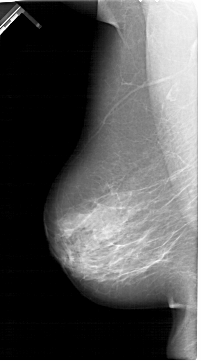

A_1390_1.RIGHT_MLO

LEFT_MLO LINES 6481 PIXELS_PER_LINE 3601 BITS_PER_PIXEL 12 RESOLUTION 43.5 NON_OVERLAY